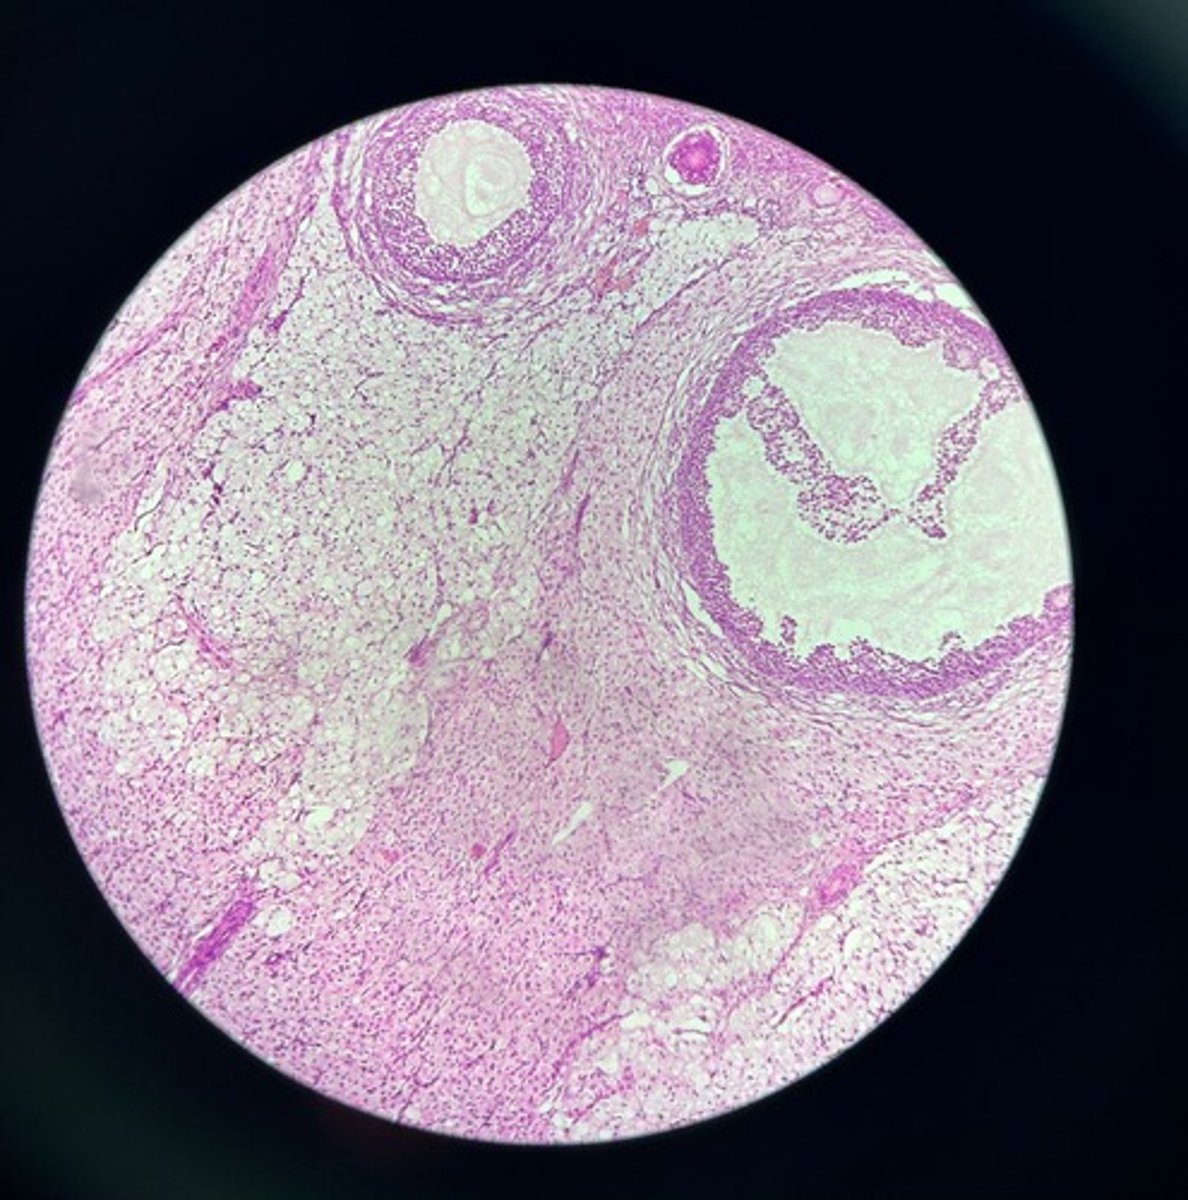

Ovary HE

Ovary HE

Ovary HE

Ovary HE

Ovary HE